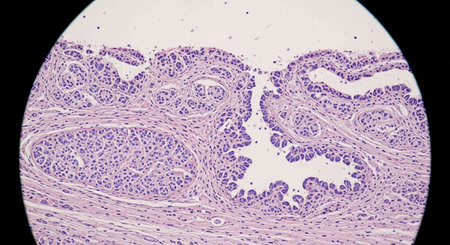

Photomicrograph showing histological features of benign prostatic hyperplasia. Enlarged prostate gland with nodular proliferation of glandular and stromal components.

Photomicrograph showing histological features of benign prostatic hyperplasia. Enlarged prostate gland with nodular proliferation of glandular and stromal components.